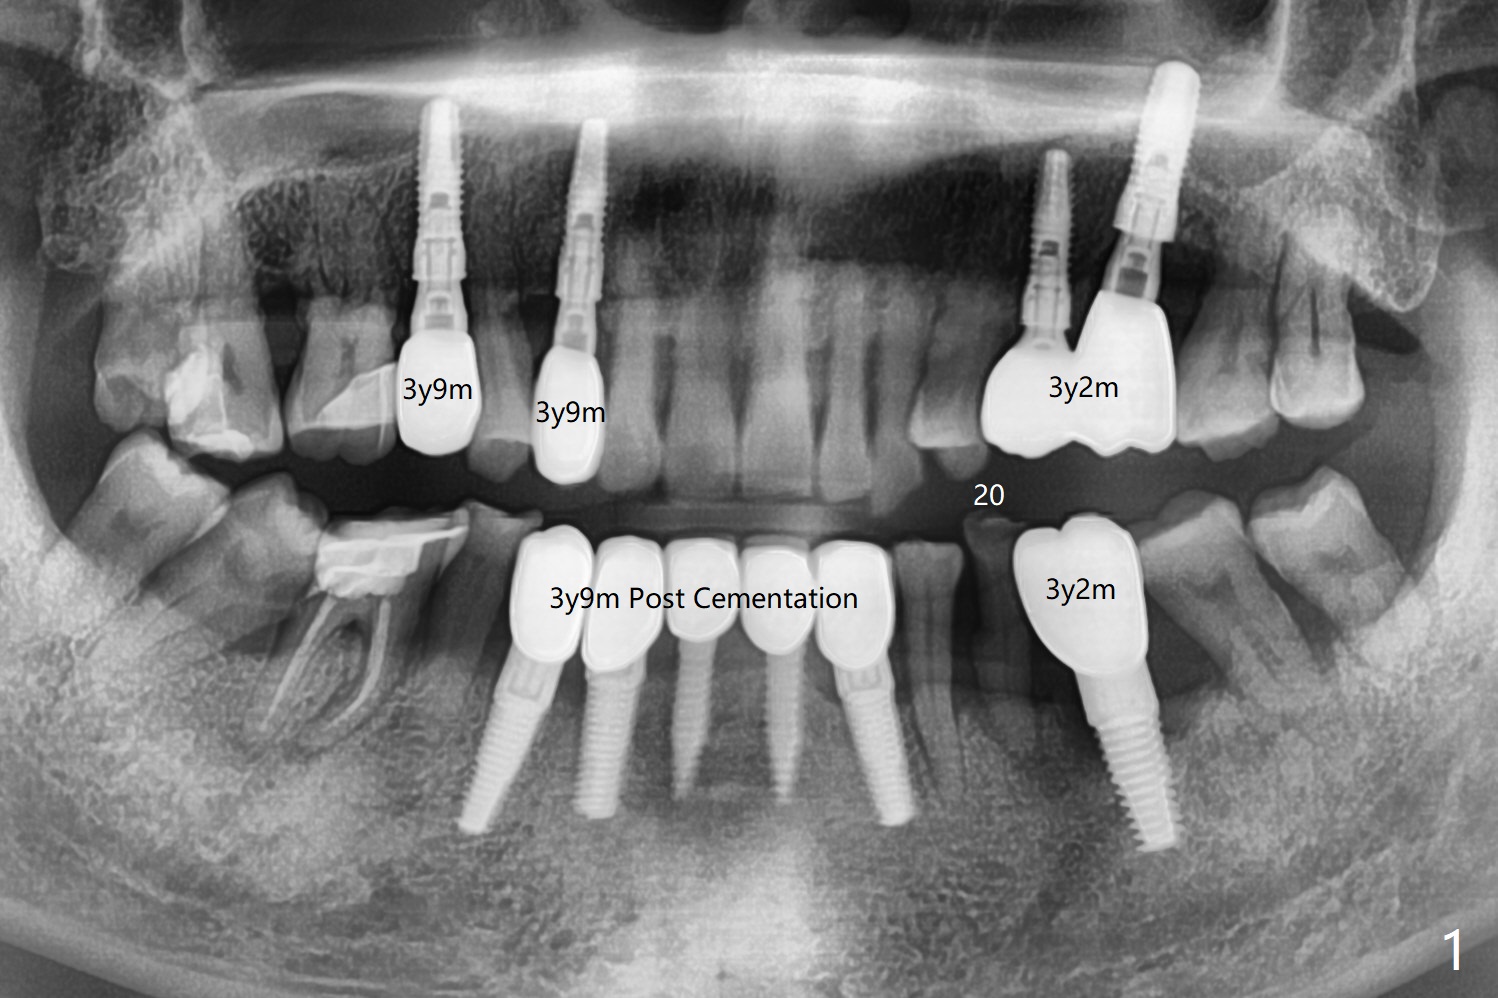

A 67-year-old man with history of chronic periodontitis and bruxism returns to clinic requesting implant for the tooth #20 with mobility (Fig.1). To assure No Deviation of implant placement, Lindamann bur will be used to remove the most coronal of the buccal aspect (Fig.2 *, 3 pink dashed line) of the thick lingual plate (L) during osteotomy. To reduce bone loss (Fig.4 *) associated with residual cement (Fig.4,5 arrowheads) of the tissue-level implants, a bone-level one (SM) will be used at #20. Check whether the nearby implant (#19) has infection clinically and bone graft if needed. Buccolingual threads of the #27 implant are also exposed 3 years 9 months post cementation (Fig.6). An ideal treatment is probably to remove the 4.5x17 mm tissue-level implant and place a 3.8x10 mm bone-level one deeper and a little mesial with bone graft.